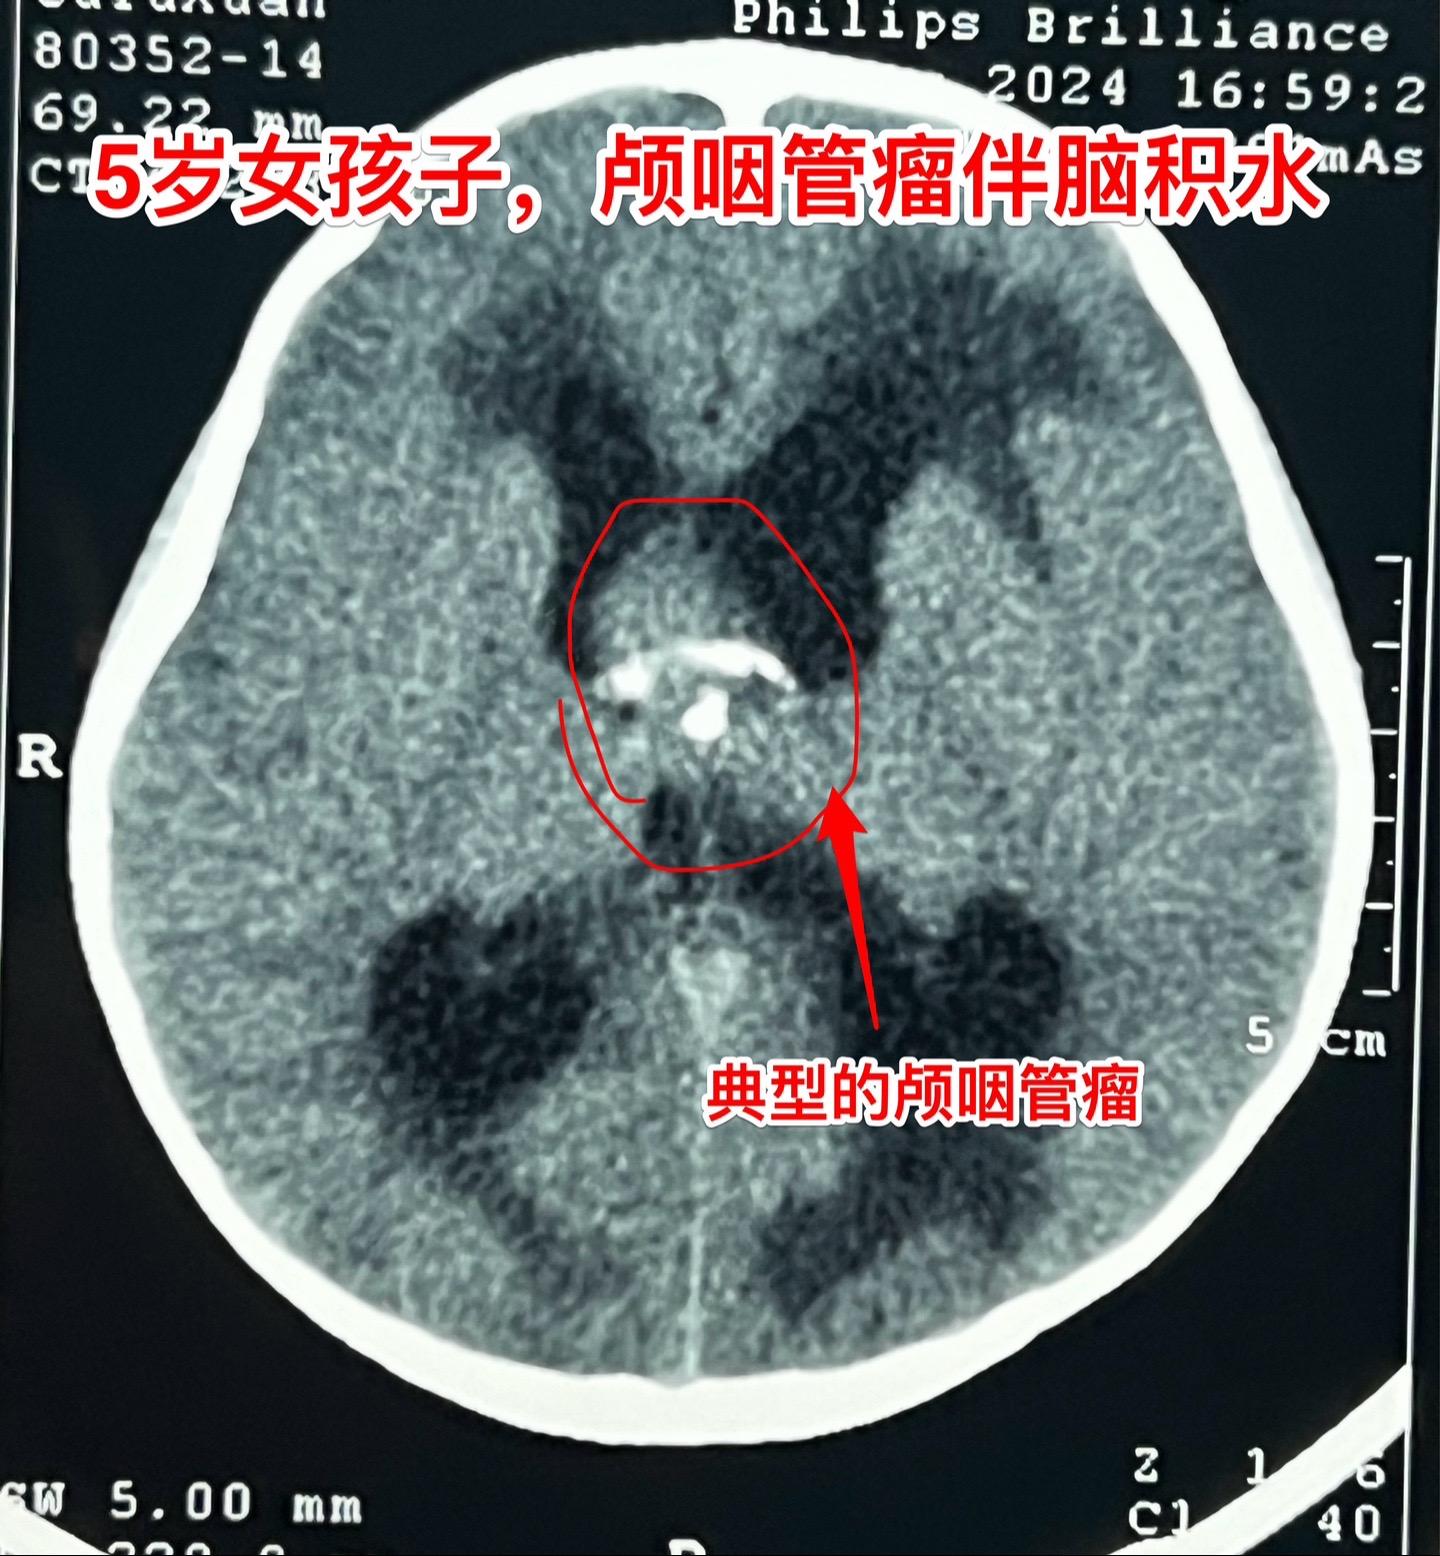

五岁商丘女孩颅咽管瘤像鸡蛋大。女孩子因为反复头痛、呕吐起病,一开始怀疑是胃肠炎,治疗后效果不好。于2024年12月18日作脑部磁共振和CT发现脑部肿瘤,怀疑是颅咽管瘤,孩子的妈妈和我加了,说肿瘤像鸡蛋那么大,焦急万分。 小孩子几经周折,最终到三博脑科医院找我办理住院手续。刚刚住院后又患感冒,发烧、咳嗽。感冒治好之后才于2025月1月7日作了手术。手术很顺利。 这个肿瘤体积大,导致脑积水,主体位于第三脑室内。对于我们科来说,这样的手术还不算是最难的。 希望小